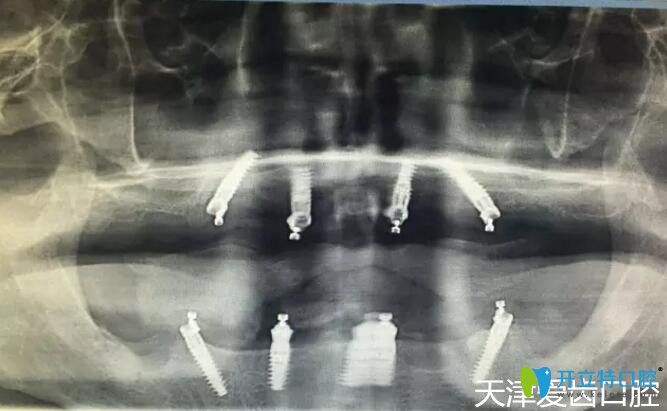

我在天津愛齒口腔做allon4全口種植牙術(shù)后CT片

郭平川醫(yī)生給我做的ALL-ON-4全口種植牙手術(shù),從拔牙到裝上臨時牙冠,僅用了2個多小時,從手術(shù)室出來我就擁有了一口嶄新的“牙齒”,而且當天下午回家就能吃東西啦!